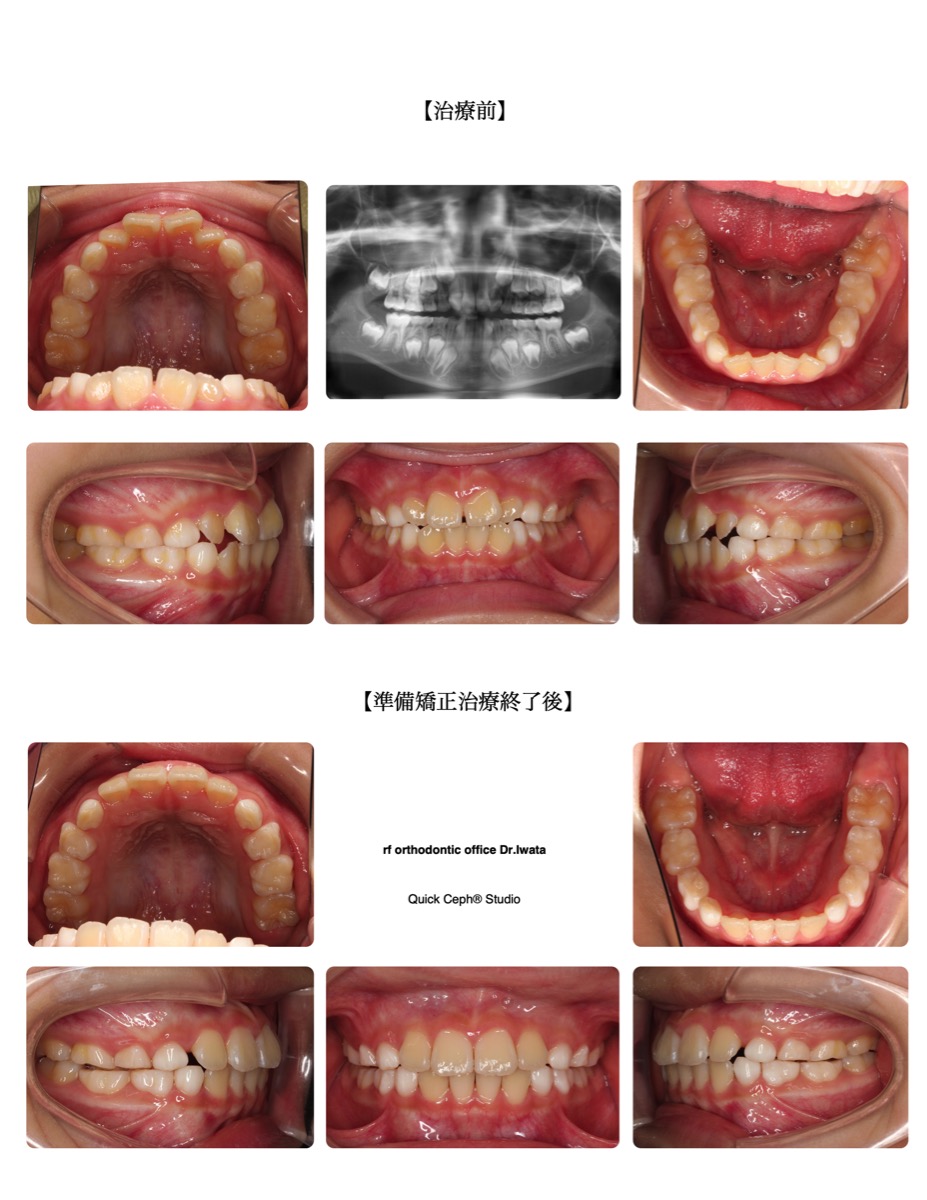

case2

出っ歯

上の前歯や上あごが前へ出ている噛み合わせ。